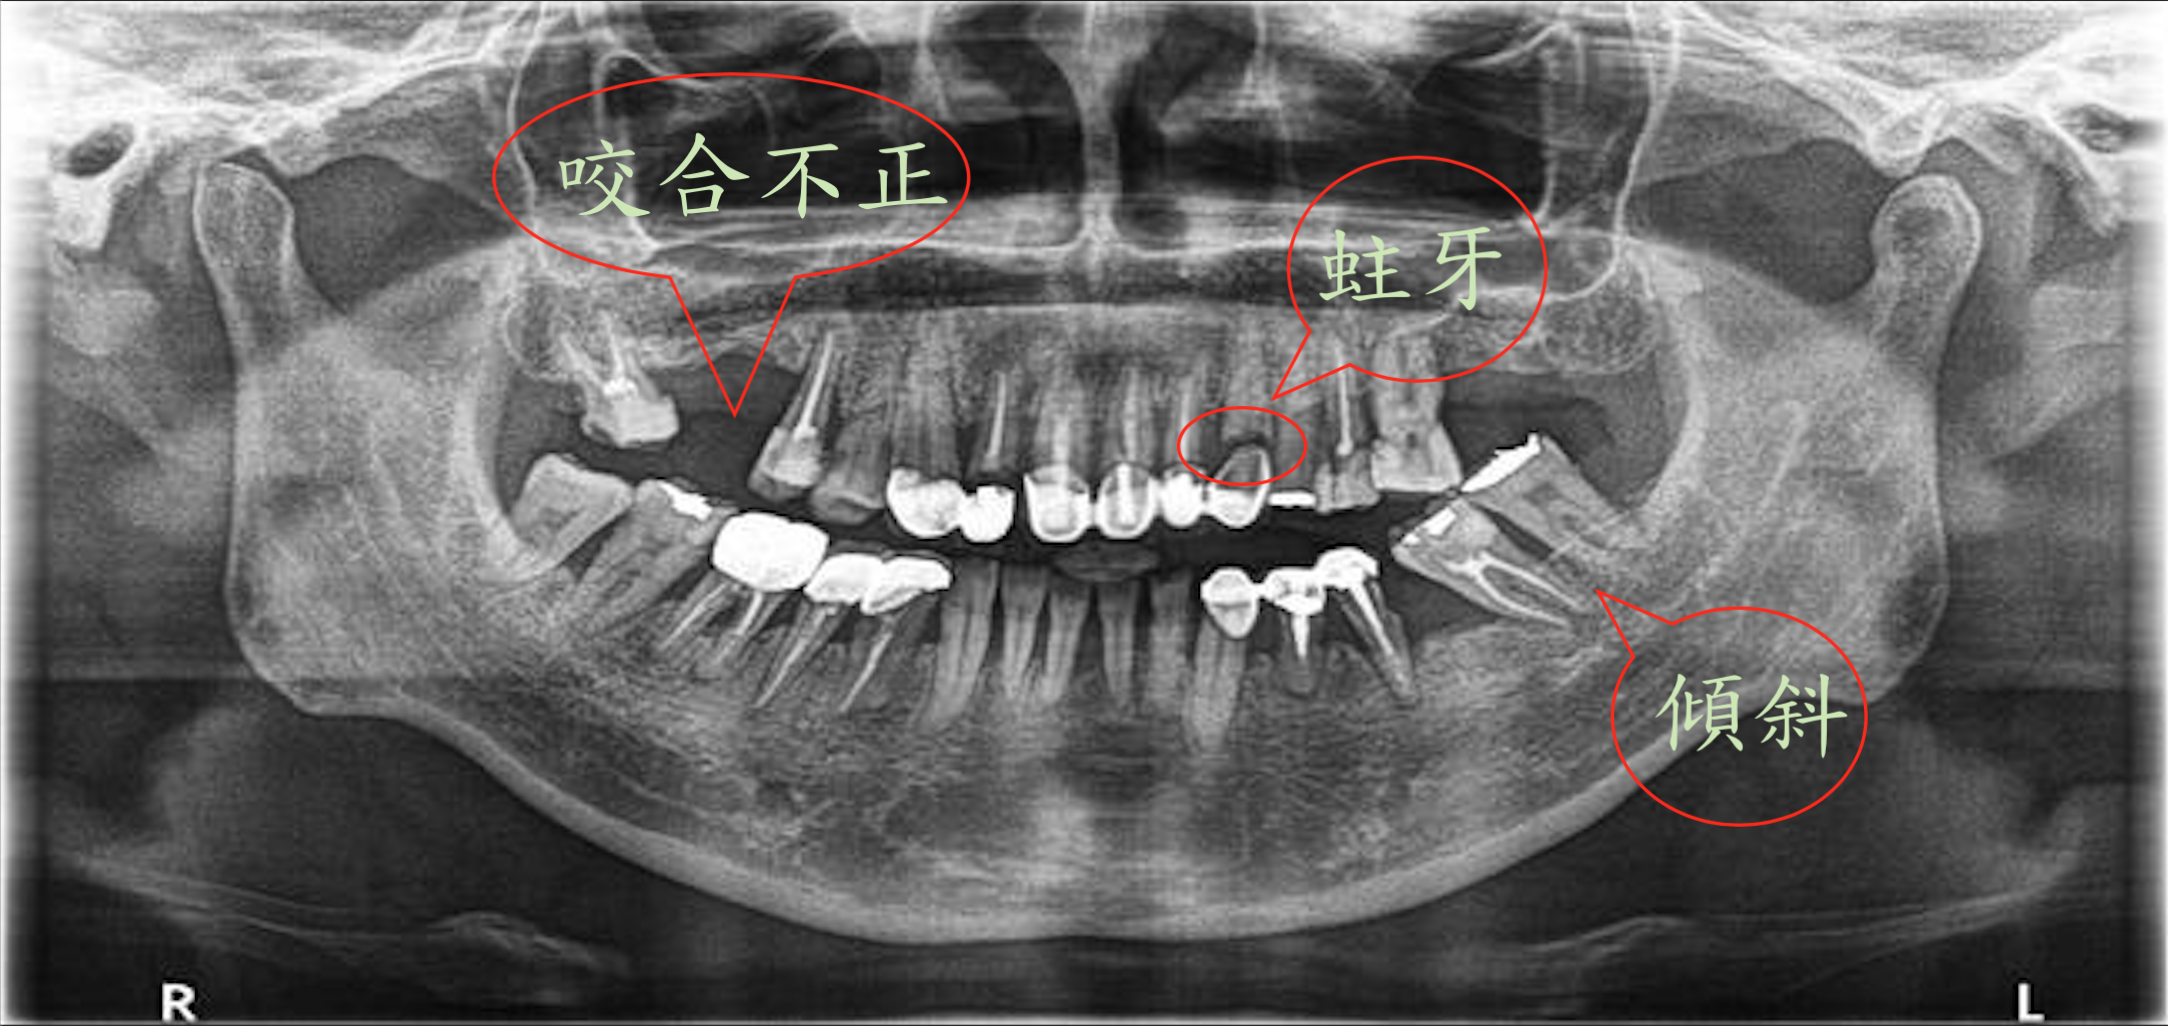

口腔缺牙的問題:

缺牙的後遺症:蛀牙、鄰牙傾斜、咬合不正(如下方x光片所標示)